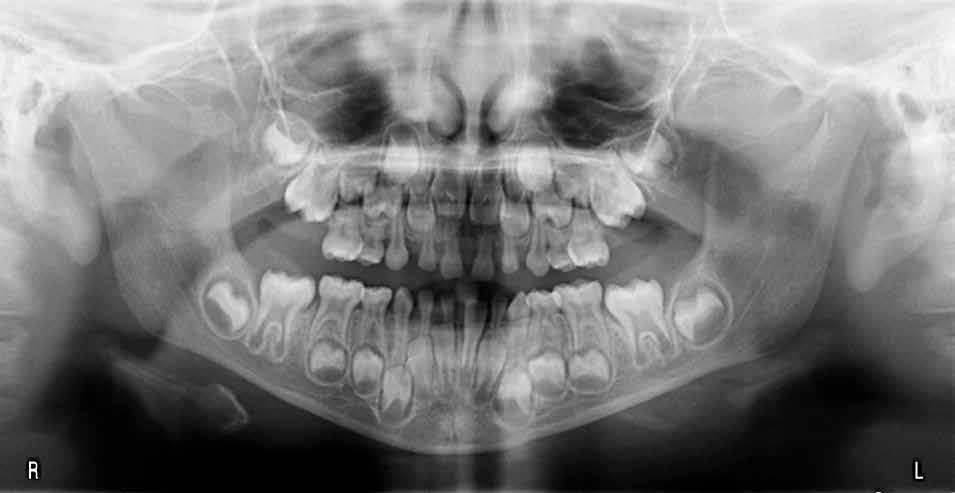

Alla risoluzione della malocclusione scheletrica e dentale si associa un netto recupero della postura con conseguente miglioramento della curva cervicale, come è possibile verificare nella teleradiografia finale.

47 46 ESTETICA FUNZIONE POSTURA Valori cefalometrici a 10 anni : ANB ANB 2.70 Posizione del Mascellare SNA 78,70 Posizione della Mandibola SNB 76.0 Angolo Articolare SArGo 142,76 Angolo Goniaco ArGoMe 125,73 Angolo incisivo inf^Corpo madibolare IiMand 92,00 Angolo incisivo Sup^Base Cranica Ant. IsCran 96,00 Angolo Interincisivo II 130,0 53 _ Esame Cefalometrico a dieci anni. 54 _ Tabella dei valori cefalometrici a dieci anni. 55 _ Ortopantomografia di controllo a dieci anni. 56 _ Teleradiografia di controllo con evidente stabilità del caso dal punto di vista scheletrico/posturale.

> La documentazione a dieci anni mostra la stabilità del caso e

come l’occlusione, elastodonticamente individuata, costituisca anche la contenzione stessa. La paziente ha smesso di

Considerazioni

indossare l’apparecchio elastodontico dopo due anni e mezzo di terapia, conservando parametri occlusali e posturali in rapporto corretto tra loro.

Nel 2019 si è provveduto all’avulsione chirurgica degli elementi dentari 18, 28, 38 e 48.

Nel caso dei pazienti di età superiore ai sei anni la documentazione precedentemente descritta sarà integrata anche con le radiografe. L’esame radiologico è assolutamente necessario ai fni della diagnosi ortognatodontica. A causa dell’età per lo più giovane dei pazienti, nella routine clinica il numero ed il tipo di radiografe dovrebbero essere stabiliti in modo da ottenere la massima quantità di informazioni con il minimo dosaggio radiologico. Le radiografe indicate per la diagnosi ortognatodontica possono essere divise in due categorie:

• radiografe per la valutazione dello status dentale, del parodonto e delle strutture ossee: ortopantomografa e radiografe intra-orali;

• radiografe per lo studio craniofacciale: teleradiografa e rx posteroanteriore.